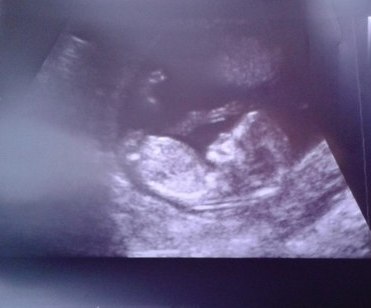

Первый скрининг прошел на ура!!!!

Вот и дожили до первого скрининга!!! Конечно было много волнений по поводу того что б ребеночек был здоровенький, ну и конечно было очень интересно посмотреть как мой малыш подрос!! До этого я его видела в виде маленькой горошины с сердцебиением, но теперь он как настоящий человечек!!! И ручки, и ножки, а буйный то какой=))))))) Надеюсь что и дальше у нас все будет хорошо=))) Теперь с нетерпением буду ждать когда снова его увижу.......Думаю в октябре нам уже скажут кто там прячется!!!!!!=))))))